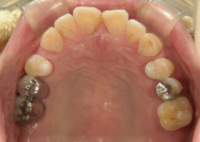

インプラントを埋入し、縫合後に次の段階へと移ります。

縫合後、インプラント違和感などがないことを確認し、アバットメント(土台)を装着します。

最後にクラウンを装着して、これでインプラント治療は終了となります(かぶせ物)。